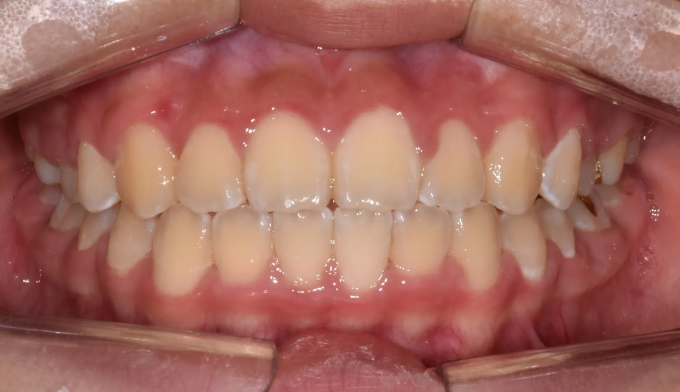

유치를 제때 뽑아주지 못하면 치아 맹출 순서가 뒤죽박죽이 되면 잇몸 안에서 맹출하지 못하게 됩니다.

본 케이스처럼 아예 치아의 각도가 누워버린 경우에는 억지로 교정장치를 부착하여 치아를 제 위치로 당겨주어야 합니다.

잇몸의 일부를 절개하여 교정장치 부착후 치아를 견인하였고 총 치료기간은 16개월입니다.

잠깐의 고생이지만 살려놓은 치아는 평생쓸 수 있는 자산입니다.